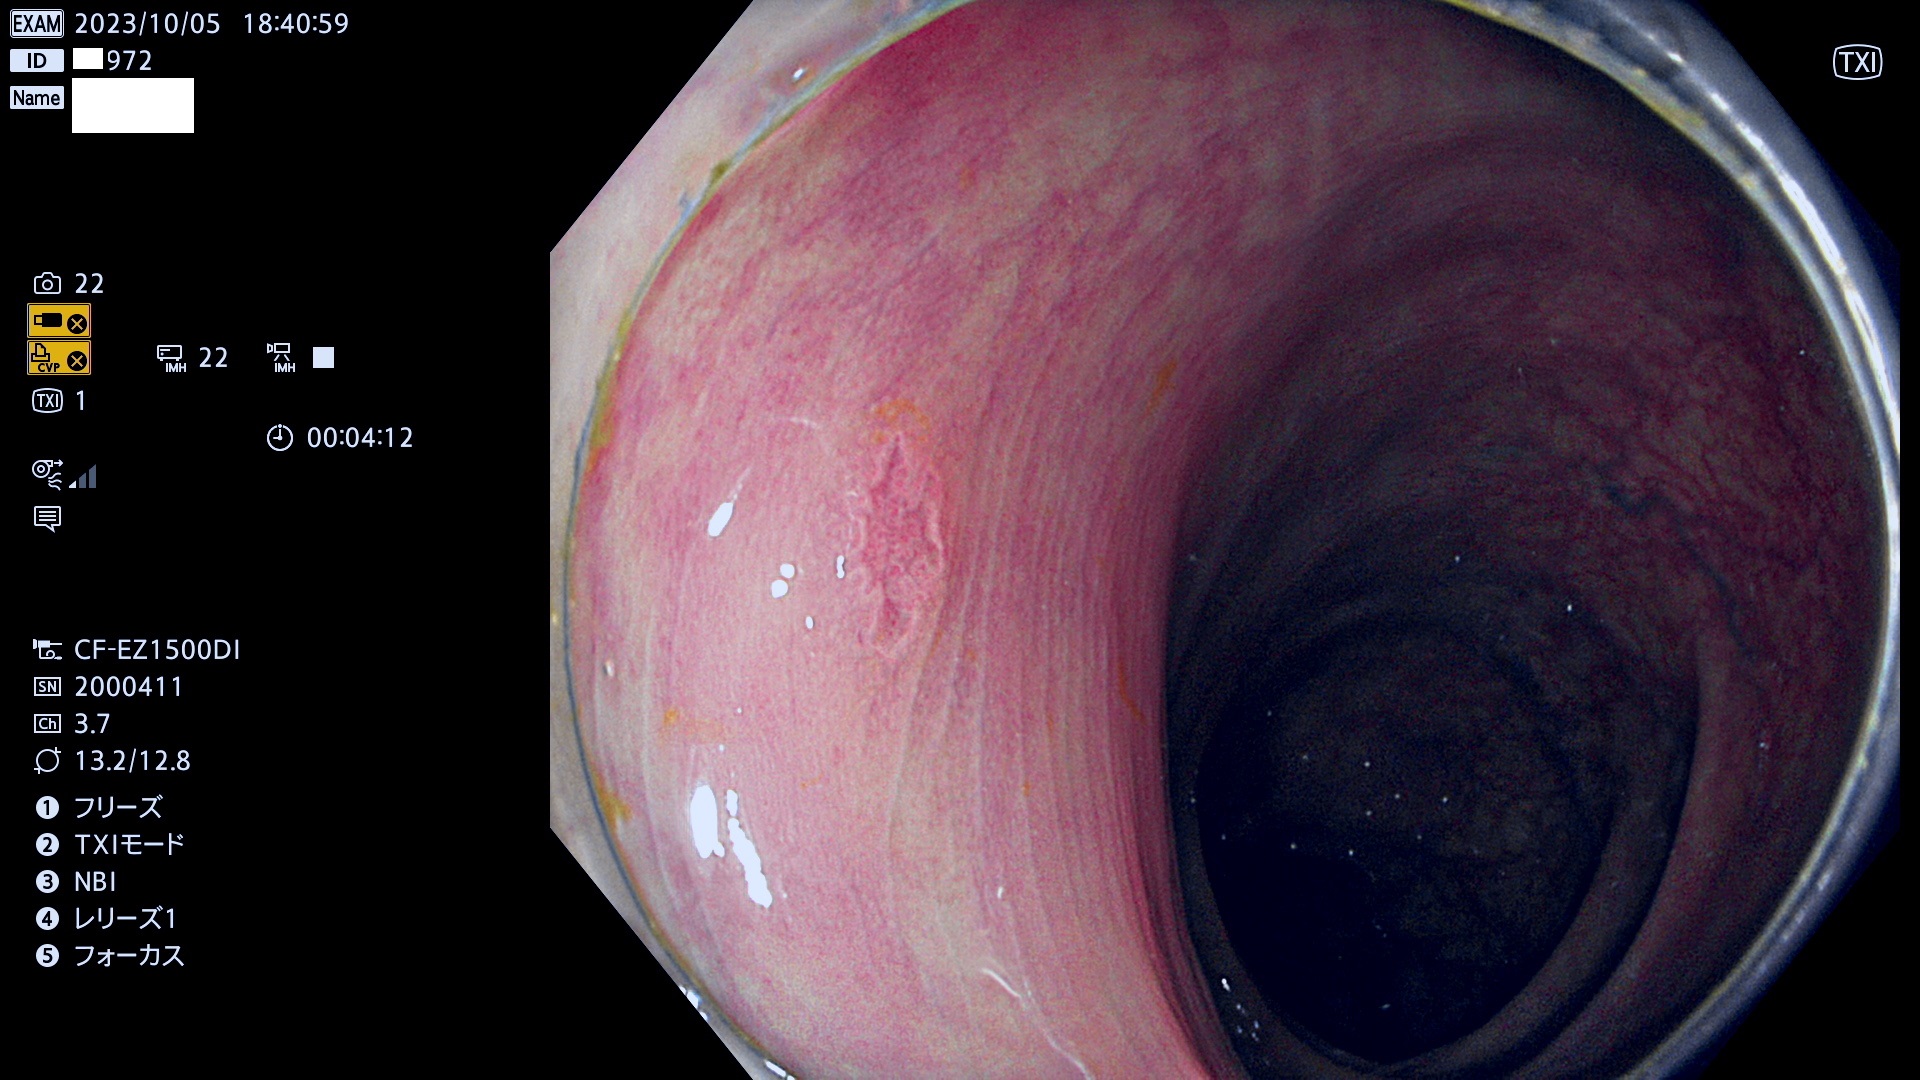

表面型腺腫(Flat Adenoma)の中で、完全に平坦な物をUb、陥凹している物をUcと呼びます。平坦隆起型(Ua)よりも、発見が難しく危険な病変です。このタイプは「内視鏡後・大腸癌の重要犯人」であり、この発見率は「腺腫発見率」よりも、重要な意味があります。

専門的)何故、陥凹していると危険? 癌遺伝子の変異が蓄積すると細胞分裂が盛んになり隆起するのでは?と通常は思われるでしょう。しかし実際は逆です。これは2022年の記事にある「細胞はストレスに直面したら細胞分裂を止める(細胞老化に入り休眠する)という生命の基本的現象」によるものです(Oncogene Stress)。細胞老化を起こすのが癌抑制遺伝子で、この安全装置(ブレーキ)が壊れると癌になります(休眠からの覚醒)。ですから陥凹は「まだ癌では無いが癌化の直前」を意味します。特に「小サイズなのに陥凹している」病変は短期間に腫瘍進化(⇒2021年記事)が起きたことを意味します(=ゲノム不安定性

専門的)Uc=De Novo癌? 内視鏡の解像度が低かった時代、このような説もありました。しかし今日の高精度内視鏡では良性の微小なUc型腺腫が日常的に見つかります。私見ですが「Ucこそが多段階発癌(Adenoma-Carcinoma Sequence)のMain Route」と考えます。

毎週の検査(木・金・土・日)に発見されたUb、Uc型・腺腫を、その週の日曜の夜にUPし1週間、提示します。

抽出の対象期間 2023年10月4日(木)〜10月9(月)の5日間(60件の検査)8件